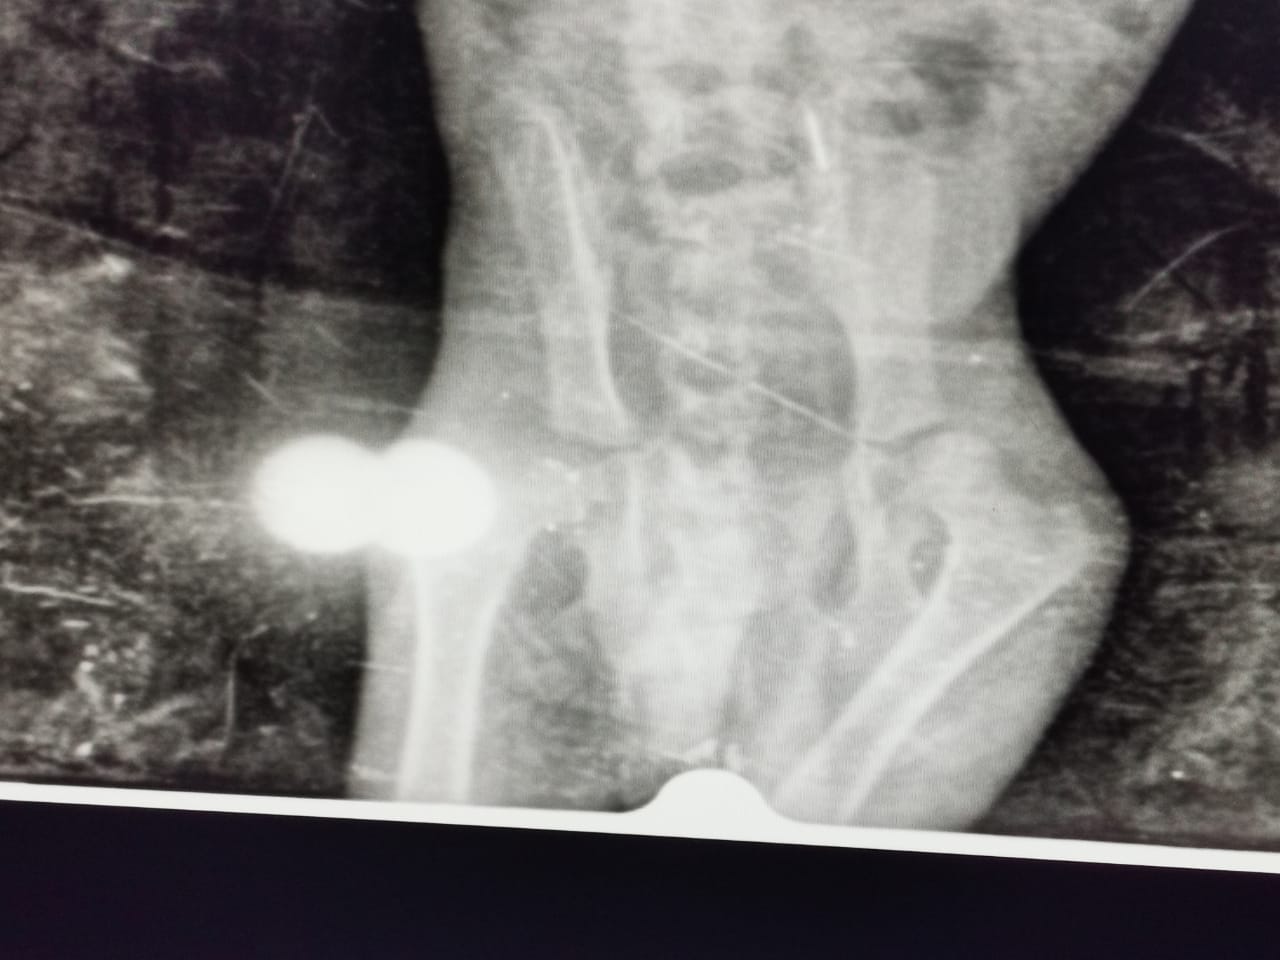

En effet, à son arrivée, nous avons constaté un problème de motricité (il ne marchait pas et pleurait de douleurs) et avons fait de suite des radios de son bassin.

Le constat n’était pas réjouissant: les hanches étaient fracturées à deux endroits et il lui fallait du Calcium mais aussi du repos, une cage basse et petite pour éviter les mouvements et pour faciliter la calcification.

Cependant, un mois après son arrivée, nous venons de refaire une radio et il y a tout de même une progression puisqu’un côté commence à se resouder.